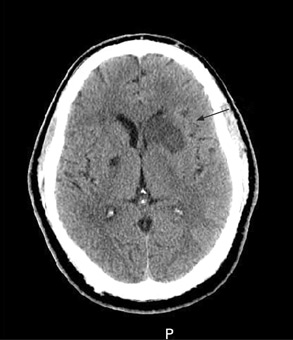

[Figure caption and citation for the preceding image starts]: Exploración por tomografía computarizada (TC) sin contraste del cerebro en que se observa infarto subagudo ganglionar basal izquierdo aislado con efecto de masa del asta frontal izquierdaCortesía de BMJ Case Reports 2009; doi:10.1136/bcr.10.2008.1139 [Citation ends].